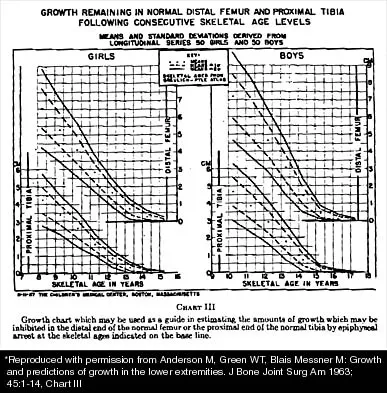

Question 54

A 10-year-old girl with a monoarticular pattern of juvenile rheumatoid arthritis (JRA) has had a 3-cm limb-length discrepancy since age 8 years when inflammation in the right knee came under good medical control. Because her right leg is longer, the patient states that she would like her legs to be close to equal in length in the future. A growth-remaining chart is shown in Figure 14. Management should consist of

Explanation